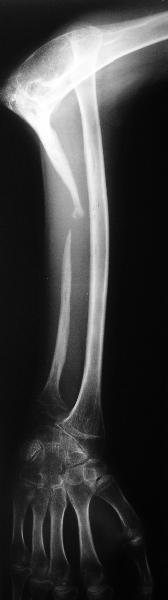

Молодой человек 2-3 года назад наблюдался по поводу прогрессирующего остеолиза правой локтевой кости. Морфологически - гемангиома, возможно, ангиомоподобный остеолиз (болезнь Gorham-Stout). Получал лучевую терапию. К настоящему времени остеолиз не прогрессирует. Однако сформировался вывих лучевой кости. Рентгенограмма и функция - см. иллюстрации. Пациенту хотелось бы улучшить функцию. Что можно предложить? Постепенное вправление аппаратом, замещение дефекта локтевой кости, резекцию головки лучевой, оставить как есть, что-то еще?

Судя по рентгенограмме, сформировался плечелоктевой артродез под углом около 90 градусов, поэтому тот объем движений, который выполняет пациент, обеспечивается за счет дефекта локтевой кости.

The free fibular graft worked well in that case and I wonder if it wouldn't be the correct thing to do in your case combined with gradual reduction of the dislocation. Certainly I cannot see how the reduction could be maintained long term unless the ulna was reconstructed. The question of how much better the patient's finction would be even with successful surgery is really difficult. I would stress potential improvements in strength rather than any promises about range of motion.